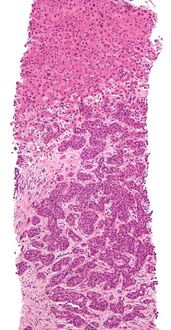

Micrograph of a liver core needle biopsy showing metastatic cancer.